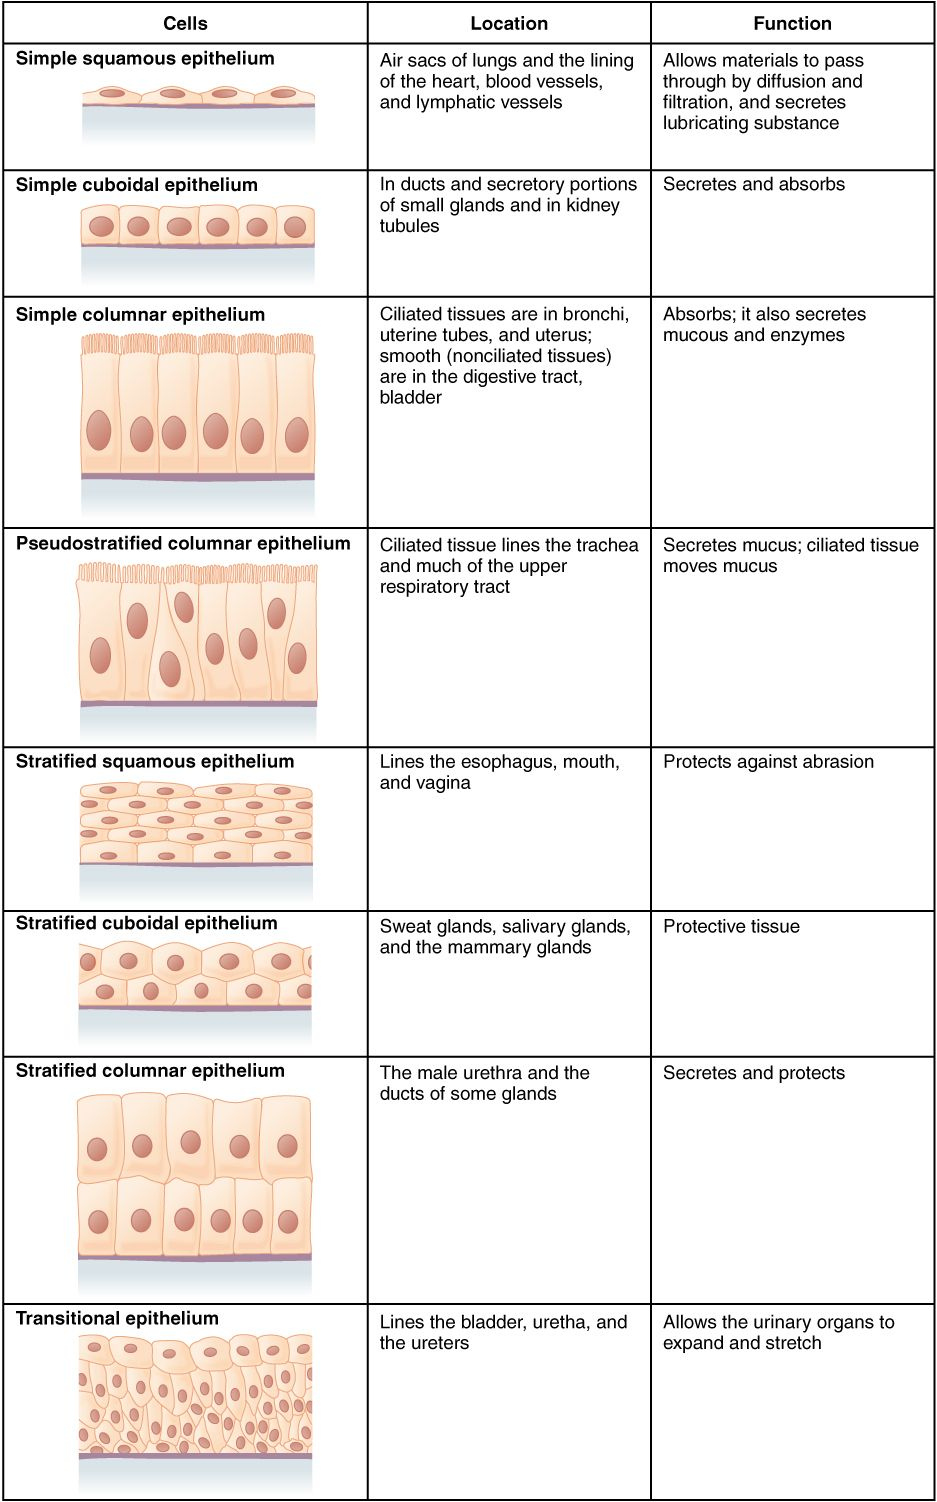

Anatomy worksheets help you find out the anatomy of various body organs. You can discover the heart’s framework and feature. For example, you can find out about the heart’s atria, which are the chambers that supply the heart with blood. You can likewise find out about the mitral shutoff, which shields the opening between the left atrium and also the ventricle.

Anatomy worksheets are likewise useful for pupils to find out about the heart. They can learn the features of heart muscle mass and how they affect the heart’s result. As an example, the heart has 2 valves, the left mitral valve and the right tricuspid valve. Besides, they can learn more about the blood circulation as well as its components.

Anatomy worksheets come in a selection of styles, consisting of color as well as identified versions. They are developed for grade school pupils. These printable worksheets are great for pupils, teachers, as well as those thinking about natural wellness, physical rehabilitation, and also massage treatment.